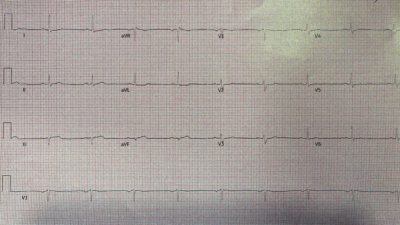

A 50-something male called 911 for acute chest pain. He had a very significant history of MI and coronary disease with multiple stents (to D1 and RCA), and history of ischemic cardiomyopathy

Medics arrived and recorded these ECGs:

ECG 1, time zero:

What do you think?

This is diagnostic of LAD Occlusion (LAD OMI).